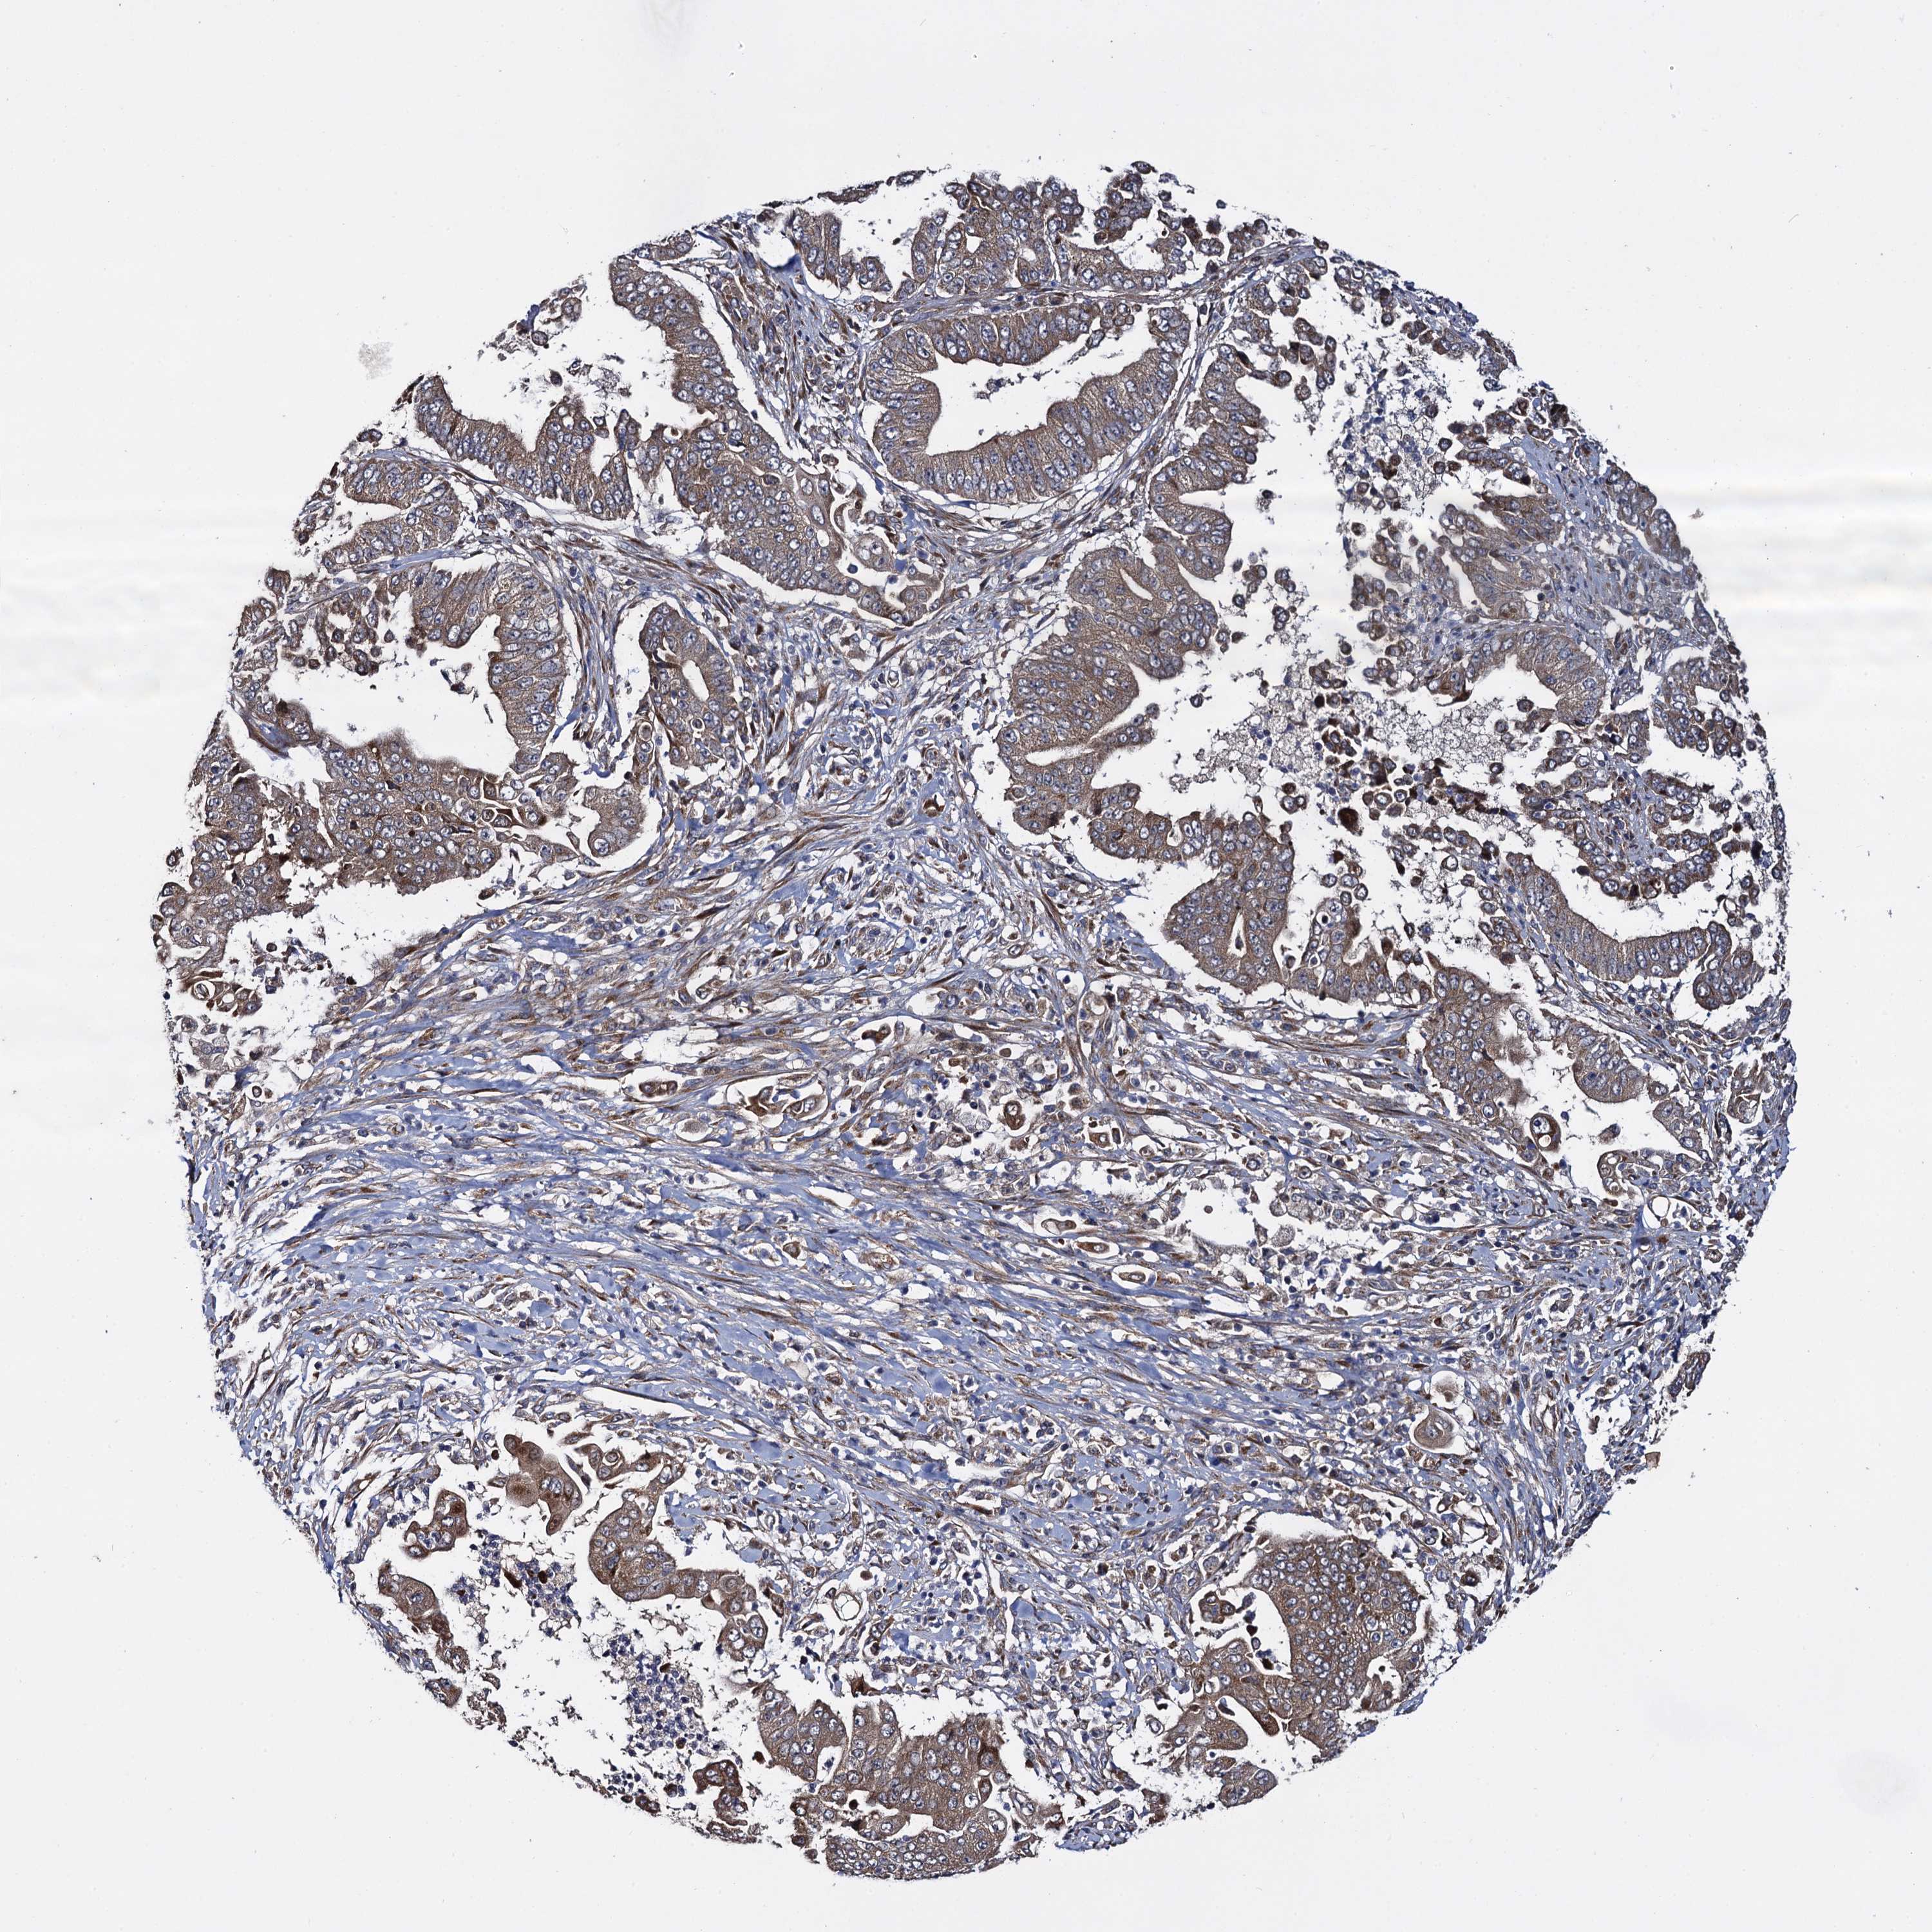

PANCREATIC CANCER - Protein expressioni

A mouse-over function shows sample information and annotation data. Click on an image to view it in a full screen mode. Samples can be filtered based on level of antibody staining by selecting one or several of the following categories: high, medium, low and not detected. The assay and annotation is described here.

Note that samples used for immunohistochemistry by the Human Protein Atlas do not correspond to samples in the TCGA dataset.

Antibody stainingi

Antibody staining in the annotated cell types in the current human tissue is reported as not detected, low, medium, or high, based on conventional immunohistochemistry profiling in selected tissues. This score is based on the combination of the staining intensity and fraction of stained cells.

Each image is clickable and will lead to virtual microscopy that enables deeper exploration of all samples and also displays staining intensity scores, fraction scores and subcellular localization as well as patient and tissue information for each sample.

Antibody HPA040601

Antibody HPA040652

Staining

High

Medium

Low

Not detected

Intensity

Strong

Moderate

Weak

Negative

Quantity

>75%

75%-25%

<25%

None

Location

Nuclear

Cytoplasmic/membranous

Cytoplasmic/membranous,nuclear

Adenocarcinoma, NOS